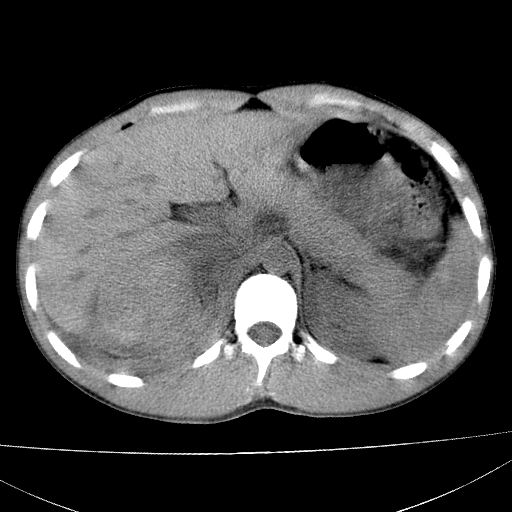

标题: CT15860:男,21岁,腹部外伤2小时伴胸疼。 [打印本页]

标题: CT15860:男,21岁,腹部外伤2小时伴胸疼。

肝脏及肾脏明显有损伤性改变并激发腹腔内积液(血),以肝脏撕裂及肾周积血显著。

1)肝破裂伴腹腔积液(血)。2)右肾破裂伴右肾包膜下及肾周血肿。3)腹部空腔脏器穿孔可能。4)右侧少量胸腔积液(血)。

肝、右肾包膜下血肿,右侧腰大肌及腹膜后血肿;腹腔少量积血;腹腔疑有少量游离气体伴肠破裂。

1肝挫伤伴腹腔积液。2右肾挫裂伤伴右肾包膜及肾后间隙肿血肿。3右肾脏周围的积气,十二指肠显示结构不清,考虑十二指肠降部破裂可能性大。